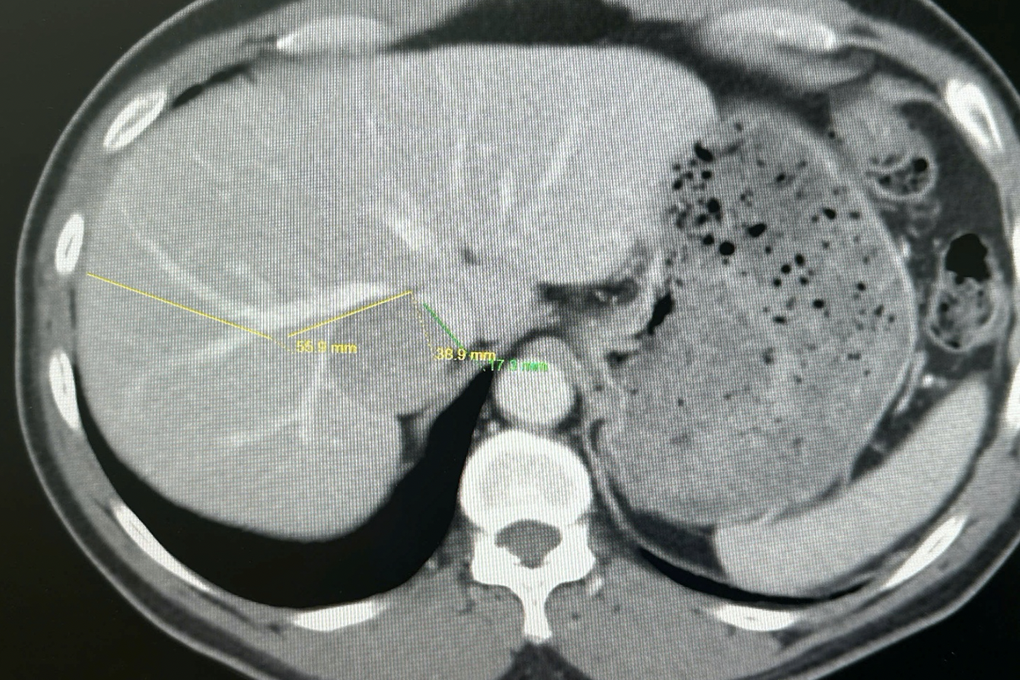

Khi vào Bệnh viện Quân y 175, qua xét nghiệm và chẩn đoán hình ảnh chuyên sâu, các bác sĩ xác định khối u gan lớn nằm ở vị trí hiểm hóc.

Khối u bị bao quanh và chèn ép nhiều mạch máu quan trọng của gan, khiến việc tiếp cận và cắt bỏ hoàn toàn trở nên rất khó khăn. Chỉ cần một sai sót nhỏ trong quá trình phẫu thuật cũng có thể gây rách mạch máu lớn, dẫn đến chảy máu ồ ạt và đe dọa trực tiếp tính mạng người bệnh.

Khối u gan của người đàn ông bị vây quanh bởi các mạch máu quan trọng (Ảnh: BV).

Sau khi tiến hành hội chẩn đa chuyên khoa, các bác sĩ Bệnh viện Quân y 175 đã xây dựng phương án phẫu thuật chi tiết, ứng dụng các kỹ thuật chẩn đoán hình ảnh hiện đại nhằm đánh giá chính xác mối liên quan giữa khối u và hệ thống mạch máu. Đồng thời, ê-kíp cũng chuẩn bị chiến lược kiểm soát mạch máu chặt chẽ để đảm bảo an toàn cho người bệnh.